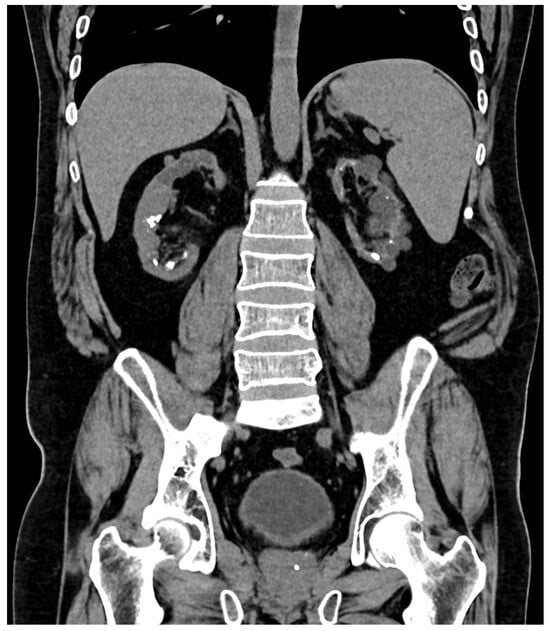

| Last imaging test | CT scan: bilateral lithiasis and microlithiasis, with nephrocalcinosis | US: bilateral microlithiasis | CT scan: atrophic kidneys with a pattern of medullary nephrocalcinosis | CT scan: microlithiasis | US: no lithiasis | CT scan: microlithiasis |